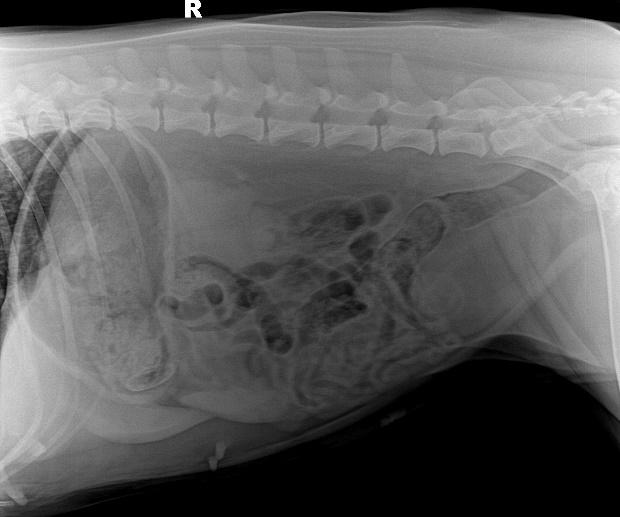

b. X射线检查:对于阻线性较强的物质(如金属、骨头)较容易辨别,对于阻线性与组织密度相似的物体较难确定,但是能够通过消化道灌服造影剂判断是否有阻塞或可包裹物体。

胃的正常大小:胃位于前腹部,隔和胆脏之后。胃排空时位于肋弓以内;从腹底算起,胃的腹侧缘大约在腹腔深度的1/3处。胃充盈时,胃向后向下延伸,与横结肠和腹底部相接。

胃内异物(金毛,手术取出6cm大衣扣子)

c.X线检查。对于阻线性较强的物质(如金属、骨头)较容易辨别,对于阻线性与组织密度相似的物体较难确定,但是能够通过消化道灌服造影剂判断是否有阻塞或可包裹物体。

机械性肠梗阻的读片要点:1.体积增大;2.形态轮廓变化;3.影像密度变化;4.浆膜细节变化。

金毛 线性异物